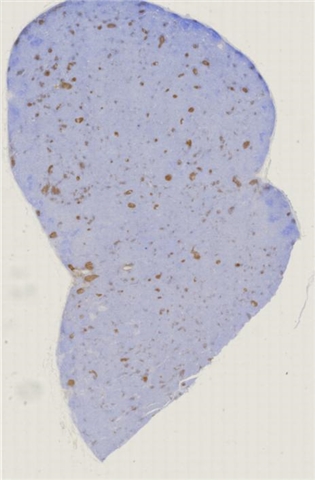

案例2 (6860)

性别:       年龄:73

患者详情: 于手术前10天无意中发现左侧大腿内侧肿物,体检肿物位于皮下,病程不详,无其他有关症状,入院后其他检查无特殊,在全麻下行肿物切除,术中肿物位于皮下

大体所见: 肿物大小3.5*3*2.5厘米

医院: 上海交通大学医学院附属新华医院崇明分院